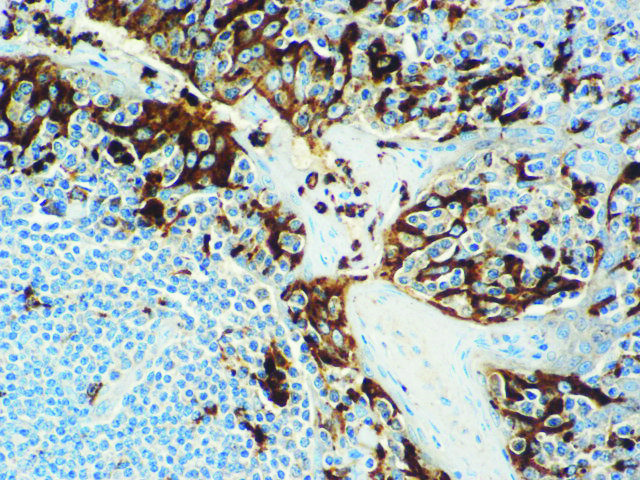

It is the ICU physician who is most likely to witness one of the deadliest manifestations of the abnormal immunological response, the cytokine storm syndrome (CSS). This response is also referred to by some as the cytokine release syndrome (CRS). CSS is characterized by continuous activation and expansion of macrophage and lymphocyte populations, which secrete large amounts of cytokines, causing the cytokine storm. This massive cytokine release is akin to hemophagocytic lymphohistiocytosis (HLH) disease, a syndrome characterized by initial unchecked and persistent activation of cytotoxic T lymphocytes and NK cells.

Clinical and laboratory manifestations of HLH include fever, enlarged liver and/or spleen, neurologic dysfunction, coagulopathy, liver dysfunction, cytopenias (i.e., low levels of erythrocytes, leukocytes, and/or platelets), hypertriglyceridemia, hyperferritinemia, hemophagocytosis, and eventually diminished NK cell activity as the immune system becomes progressively paralyzed. HLH can be familial (primary HLH) or secondary to another disease process (sHLH), such as rheumatic disease, in which it is referred to as macrophage activation syndrome (MAS, characterized by elevated ferritin).

This activation induces inflammatory monocytes to highly express IL-6, starting a localized and then systemic cascade effect that results in hyperproduction of IL-6, which accelerates the inflammatory process. Because IL-6 also increases vascular permeability, excessive levels cause blood vessels to become very leaky. This, along with clotting factors released from vascular endothelial cells, stimulates the coagulation cascade, resulting in microthrombosis (tiny clots), which leads to ischemia and tissue death of the kidney, intestines, heart, liver, brain and extremities.